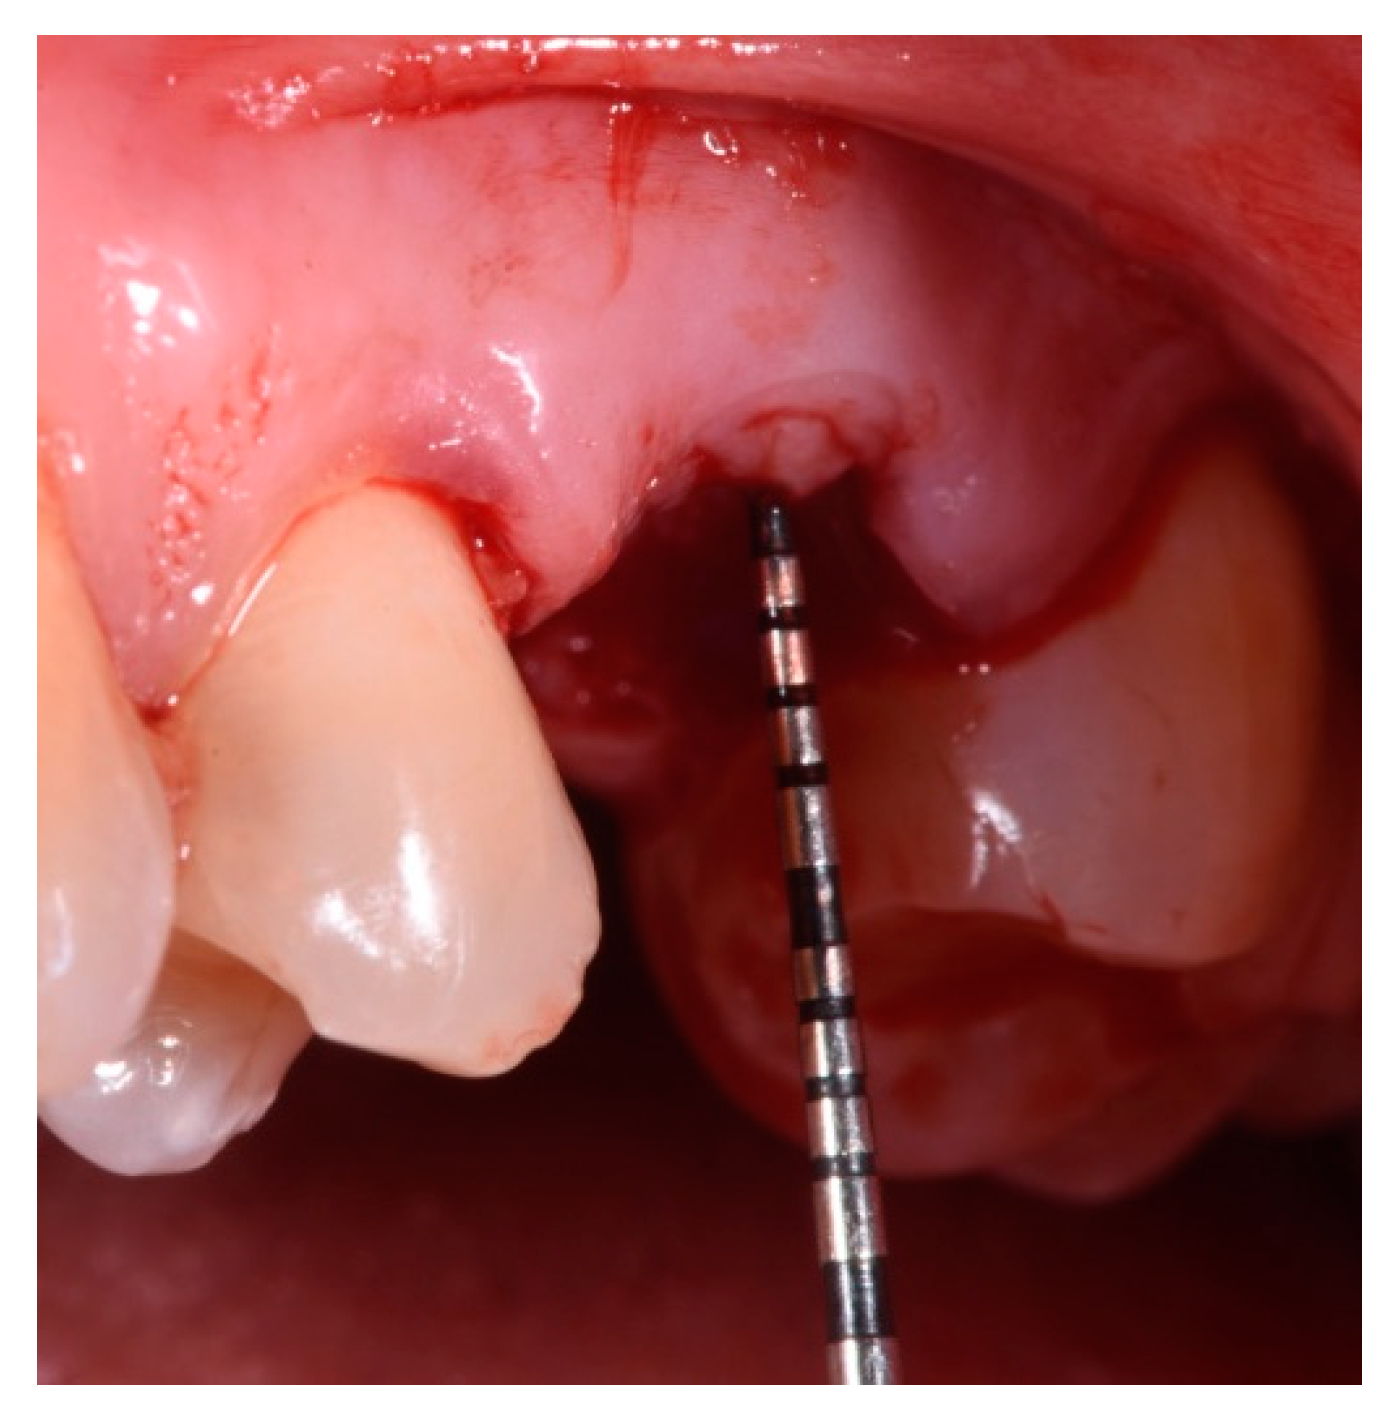

- Measurement in mm of the depth of insertion of the instrument into the gingival sulcus;

- Periodontal probing to assess the presence of the buccal plate.